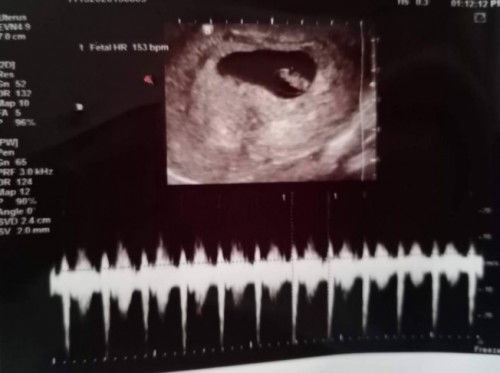

Kala ko may yeast infection ako nkapag insert ako ng garlic sa vagina ko mga 2 hrs. Noong nglockdown,kaya ngsearch ako ng home remedy. Di ko alam na buntis na pala ako nun ng 6 weeks. Hindi kaya yun makakaapekto sa pinagbubuntis ko nun. Sobrang nag alala kasi ako bka makakaapekto un sa baby. Lagi ko naiisip un, nastress na ako.😥😢 #firstbaby #1stimemom #adviceplsss